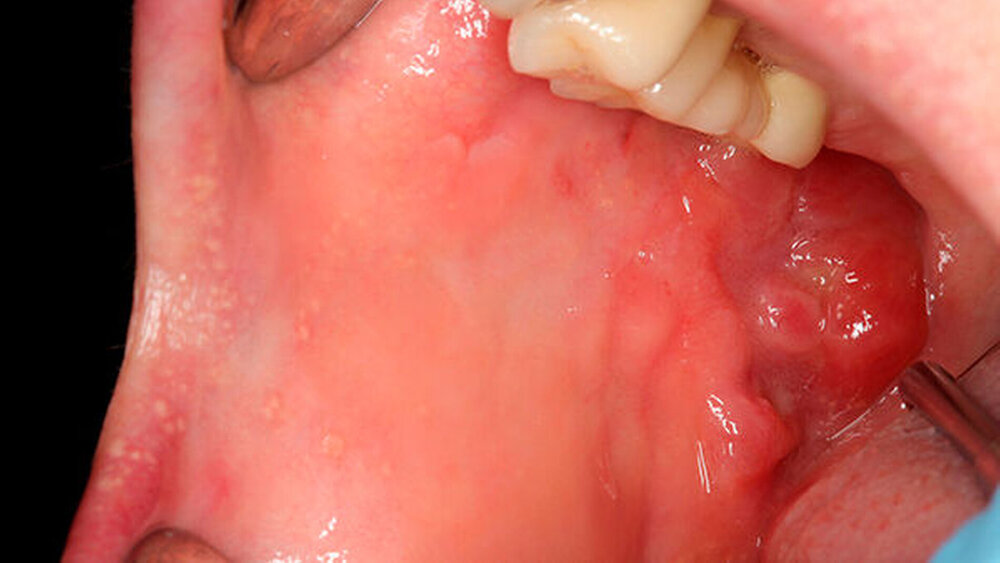

Es ist sehr wichtig, rechtzeitig eine differenzialdiagnostische Abwägung zwischen einer aphthösen Läsion und anderen ulzerösen Läsionen zu treffen, um präkanzeröse Vorläuferläsionen im Mund- und Rachenbereich zu erkennen.

Dies ist notwendig zur Prävention der Entstehung eines oropharyngealen Karzinoms beziehungsweise um die Diagnose bereits im Frühstadium zu sichern, denn eine Therapieverzögerung von mehr als vier Wochen führt bei oropharyngealen Karzinomen zu einer signifikant schlechteren Überlebensrate [Allison et al., 1998; Kowalski et al., 2001], aber auch zur Notwendigkeit der Anwendung multimodaler und aggressiverer Therapiestrategien.

Zugrunde liegende Erkrankungen und ausdrücklich neoplastische Vorläuferläsionen oder ein manifestes Malignom sind insbesondere im Erwachsenenalter differenzialdiagnostisch auszuschließen.

Bei länger als 14 Tage bestehenden Läsionen im Erwachsenenalter ist eine Biopsie obligat, vor allen Dingen wenn klinisch keine eindeutige Zuordnung zu habituellen Aphthen (Typus minor) möglich ist.

Entsprechend der S2k-Leitlinie Diagnostik und Management von Vorläuferläsionen des oralen Plattenepithelkarzinoms in der Zahn-, Mund- und Kieferheilkunde [AWMF-Register Nr. 007/092, Kunkel et al., 2010]) ist eine Abgrenzung von Vorläuferläsionen zu morphologisch ähnlichen Erkrankungen der Mundhöhle und des Rachens, zu denen auch die rezidivierenden oropharyngealen Aphthen gehören, erforderlich.